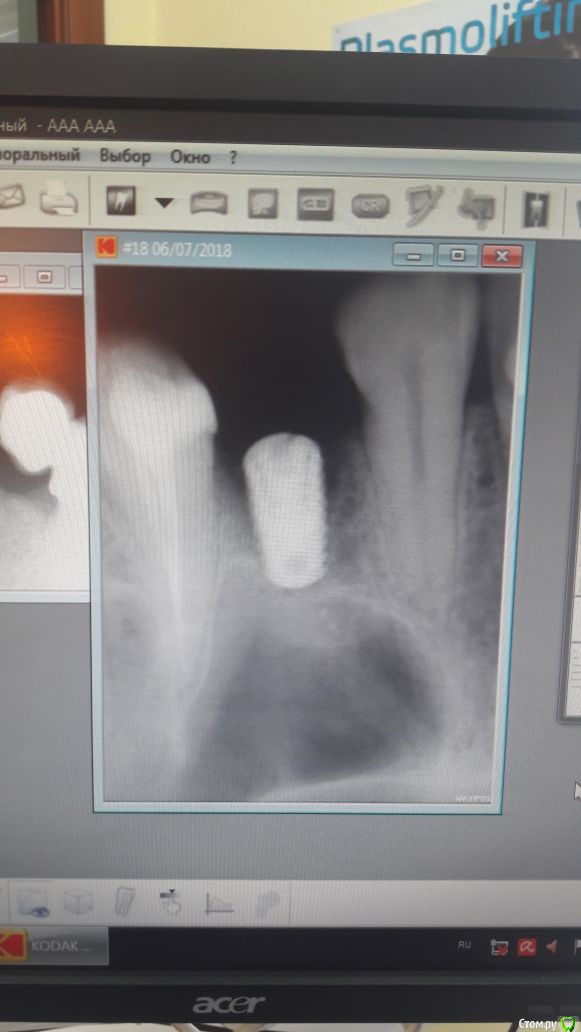

Игорь Надель Опубликовано 13 июля, 2018 Поделиться Опубликовано 13 июля, 2018 Установка импланта AnyOne 4.0 х 8мм, 2 сегмент зуб 24 места по горизонтали и по вертикали достаточно, сверление по протоколу, кортикальное сверло не использовал. Первичную стабилизацию получил, ушил нить 5/0 через шесть дней на приеме увидел что шов дистальный разошелся. контрольный снимок никакой явной патологии и проблемы не показал. Через месяц 2 снимок обратилась с жалобами на гнойничок над имплантом, вскрыл промыл установил формирователь. Ваше мнение выкрутить или оставить. если оставить то дальнейшие действия Ссылка на комментарий

Bier Опубликовано 13 июля, 2018 Поделиться Опубликовано 13 июля, 2018 имплантат недозаглублен. Выкручивайте и ставьте нормально. Места кстати по высоте было изначально недостаточно, вы сделали замеры, увидели 8мм кости и закрутили, но это неправильно. 2 Ссылка на комментарий

Игорь Надель Опубликовано 13 июля, 2018 Автор Поделиться Опубликовано 13 июля, 2018 имплантат недозаглублен. Выкручивайте и ставьте нормально. Места кстати по высоте было изначально недостаточно, вы сделали замеры, увидели 8мм кости и закрутили, но это неправильно.Имплант установлен вровень с костью, это был предпоследний снимок, потом было проведено докручивание. По КТ место было 7,79, поэтому был выбран имплантат 8 мм и закручен бикортикально. Что было не верно 1 Ссылка на комментарий